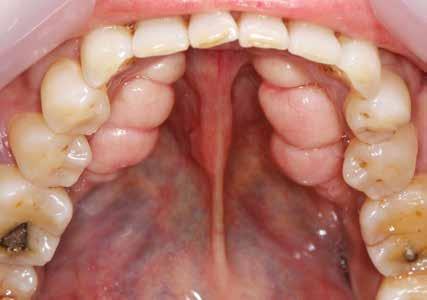

Den kliniske undersøgelse viser harmoniske ekstraorale sagittale forhold med skeletalt dybt bid (Fig. 1A, D). Hendes smil er alderssvarende med en eksponering på 8/10 af overkæbeincisiverne, mens smilets bredde er smalt med synlige mørke laterale rum (Fig. 1D). Underkæbeincisiverne er synlige under tale. Der ses neutrale okklusale forhold ved hjørnetænderne og neutrale pladsforhold i overkæben, men udtalt trangstilling i underkæben især lokaliseret i regio 1-1 (Fig. 1C).

Sliddet klassificeres som grad 2 (moderat tandslid) på de centrale incisiver i overkæbe og underkæbe. Det kan anses som patologisk, da det er atypisk for patientens alder, giver anledning til smerte/ubehag, og giver patienten et æstetisk problem. Der ses infraktioner af overkæbeincisiverne. Der ses endvidere en udtalt Spee-kurve i underkæben og ingen interincisal afstøtning på 2-2 med let ganepåbidning.

Der ses anterior trangstilling i begge kæber og overerupterede 1+1 og 2,1-1,2, hvilket resulterer i dybt bid med 2- tæt på ganepåbidning. Der er normale sidetandsrelationer, men der ses 5 mm horisontalt overbid (HOB) og 7 mm vertikalt

overbid (VOB). Papillen mellem 1+1 er betydeligt reduceret pga. fæstetab, og de mesialt kippede 1+1 har resulteret i en ”dark triangle”. Den facioorale funktion er for nuværende i.a. Panoramarøntgen (Fig. 1, I) viser marginalt knogletab i begge kæber og fravær af 8,7+7,8 og 8,7-8.